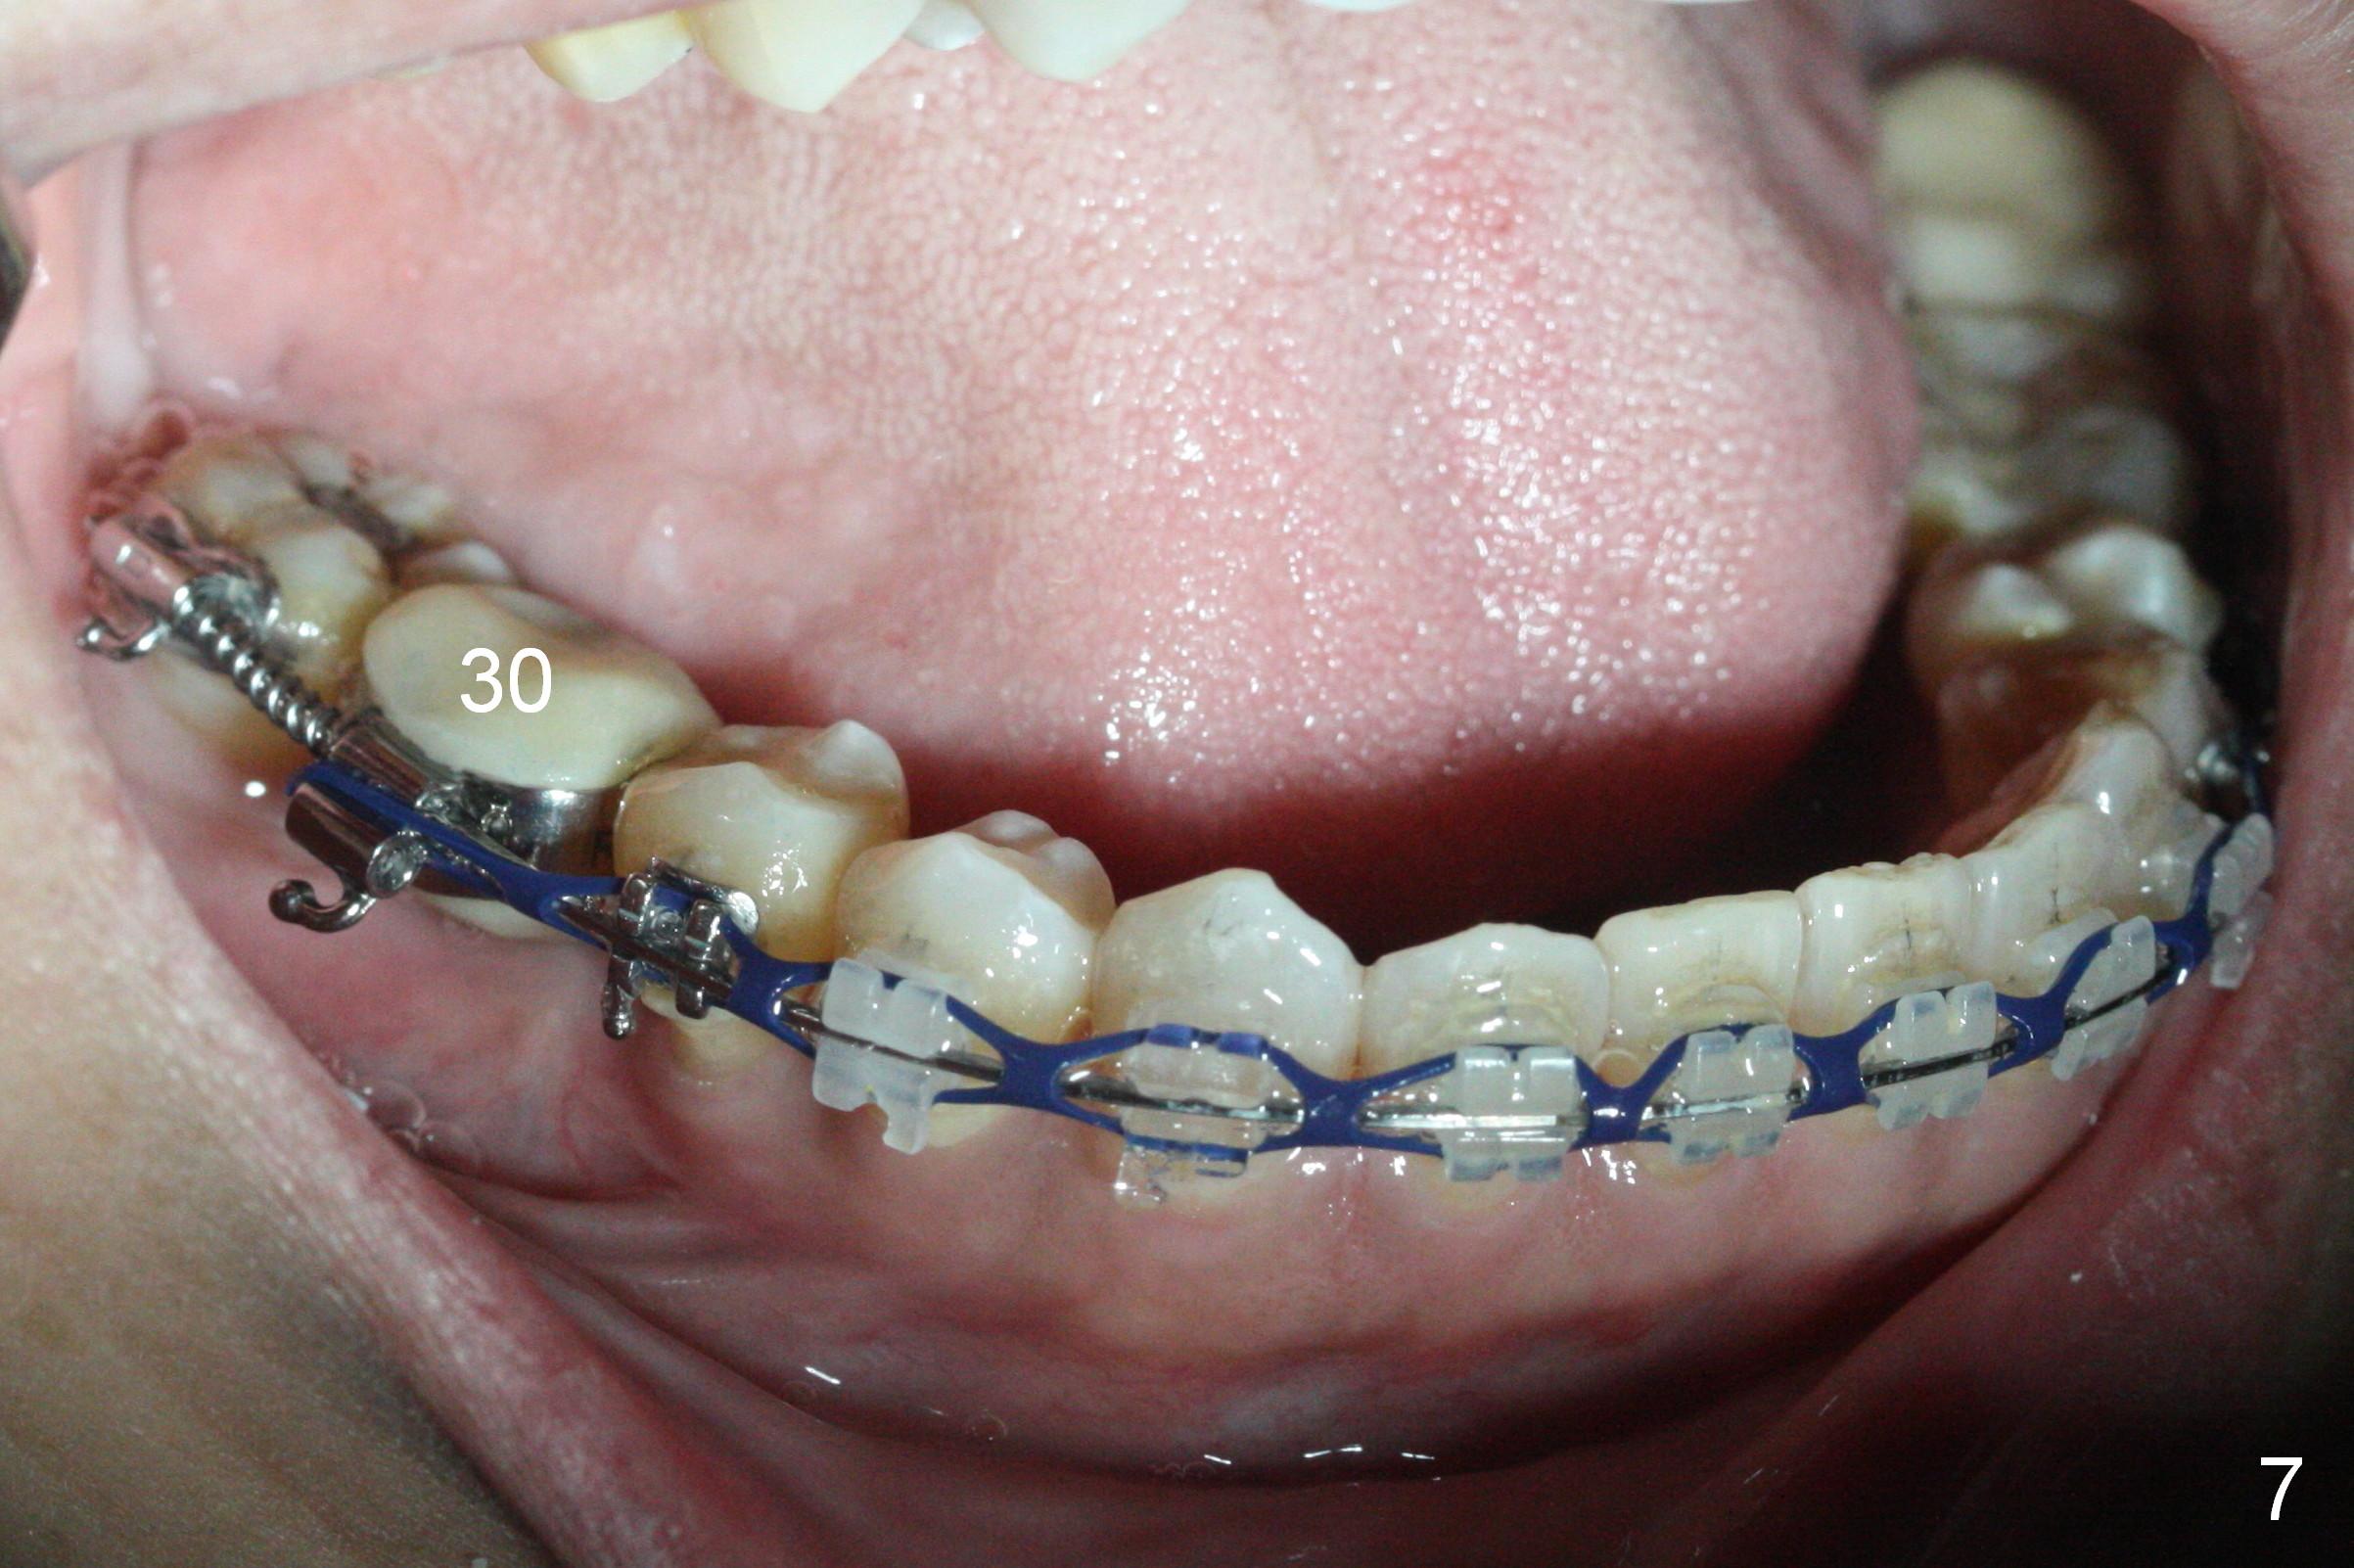

A provisional is fabricated 1 month postop to prevent the tooth #31 from rotation under the tension of the open coil spring, as mentioned above. Acrylic is added distal for #31 distalization nearly 2 months postop. More definitive orthodontic action begins 3 months postop (Fig.7, banding and open coil spring). The edentulous space increases to satisfactory width 3.5 months postop (Fig.8). A normal sized crown is delivered 4 months postop (Fig.9). The patient is pleased with the new tooth (Fig.10 nearly 6 months post cementation). There is no bone loss 13 months post cementation (Fig.11 (pan), 12 (CT coronal section (L: lingual))).